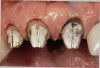

Figure 3  Dark teeth or teeth requiring restorations that are more opaque for masking often require the margin to be carried subgingivally, as with this central and lateral incisor.

Figure 3

The most common reasons to extend a margin below tissue are: caries below gingiva; old restorations that already exist below gingiva; to achieve adequate tooth preparation length for proper retention and resistance; to make significant contour alterations; to hide the margin when the tooth is discolored (Figure 3 and Figure 4); and to hide the margin when the restorative material of choice demonstrates optical properties different from those of the natural tooth such that the margin would be highly visible. Regardless of why a subgingival margin is chosen, there are 2 negative responses that may occur.